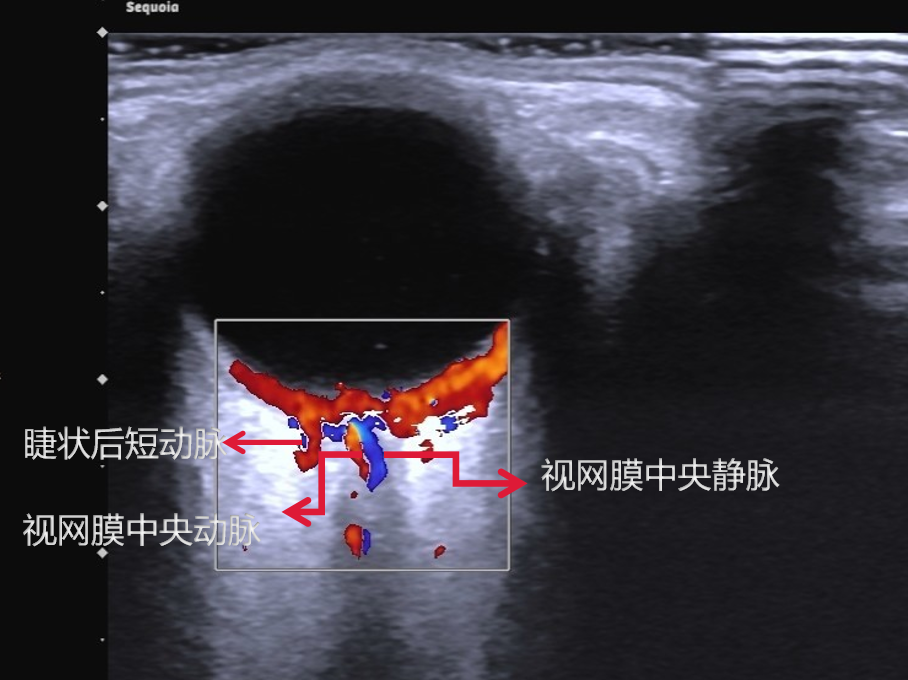

在视神经内视网膜中央动脉和中央静脉伴行, CDFI 可见视神经内红蓝相间的血流信号(图 3 ),频谱显示视网膜中央动脉呈斜三角形,也呈三峰两谷型,峰谷之间差距不明显,峰速约 7 ~ 14cm/s(图 4 )。

图 3 视网膜中央动脉与静脉

图片来源:作者提供